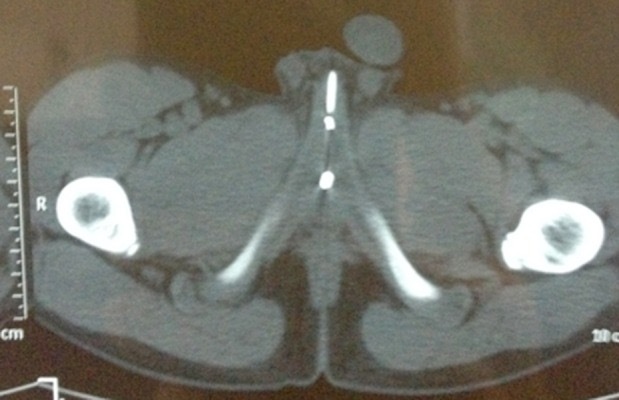

КТ-без контраста показало сверхплотное металлическое инородное тело (вскрытая английская булавка) в бульбарной части уретры спереди-ниже лобкового симфиза. Не было никаких признаков образования периуретральной гематомы.

Figure 3. КТ-изображение малого таза показывает сверхплотное металлическое инородное тело (открытая английская булавка) в бульбарной части мочеиспускательного канала. Признаков образования периуретральной гематомы нет.